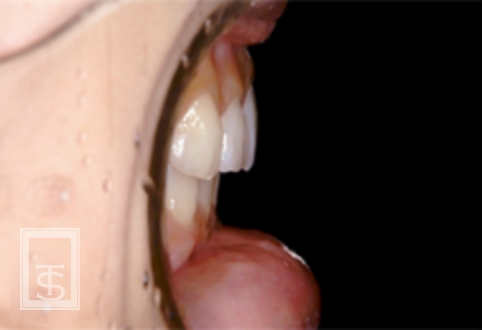

スマイルライン(Smile line)

唇、歯肉、前歯により影響を受けるのがスマイルライン(Smile line)です。

歯の排列位置によって調和のとれた笑顔が獲得されます。